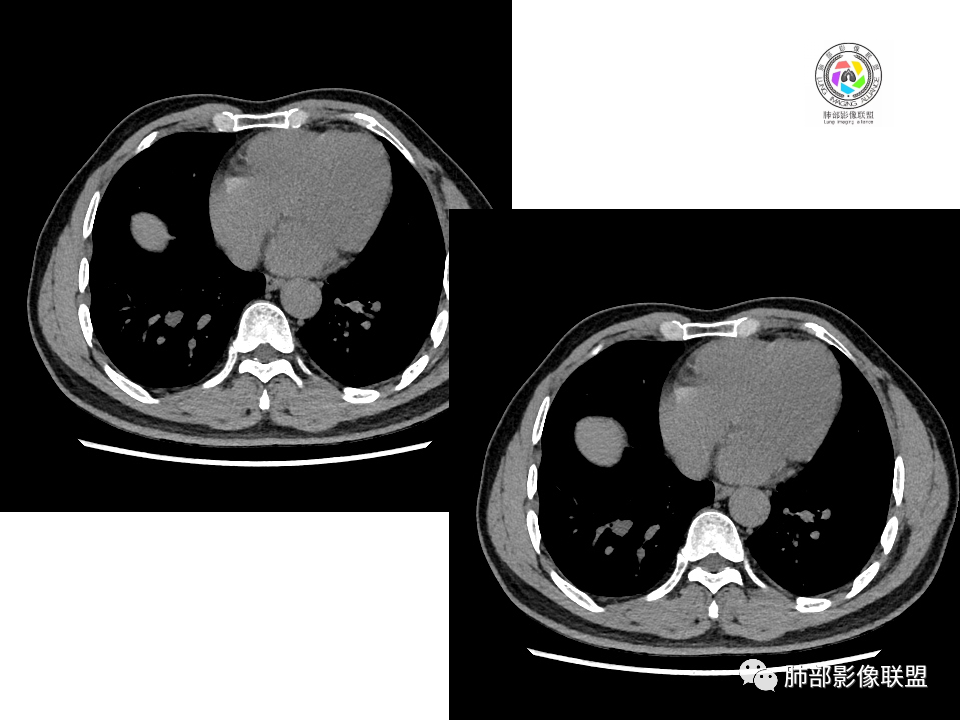

右肺下叶占位,胸膜下,与胸膜关系密切;

密度均匀;糊墙,边缘膨隆为主;

部分血管推移。

支气管如何?

秦化君: 似乎无关

张燕萍: 没看到堵塞哦落花时节: 没看到支气管进入南边:好,都在门口。

浅分叶

这个结节呢?

血管也是稍推移,在边缘,病灶密度均匀,边缘稍收缩;均匀强化;

这两个病灶的密度、强化、形态、边缘、与血管的关系类似;还是一元论吧。

右肺中叶病灶

GGO,与支气管关系密切

这个形态、与支气管关系,与前两个不一致,所以考虑独立炎性病变。